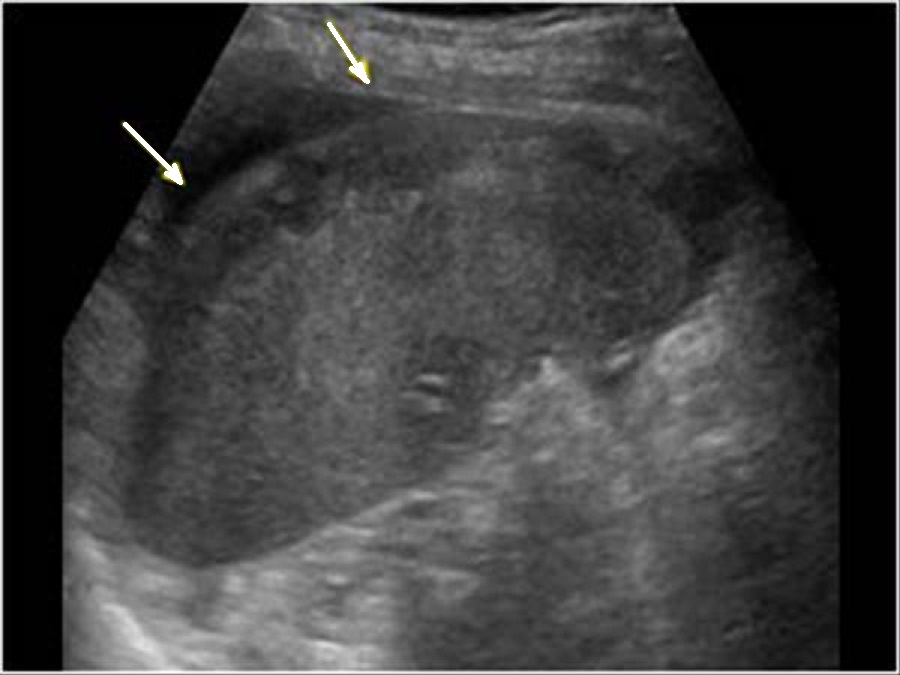

Image echographique d'une autre

traumatisme de la rate de grade II avec aspect

de laceration casulaire profonde et des hematomes

hypoechogene intra-patenchymateuse .

Complication hemoperitoine peri-capsulaire localise

peut en s,observer ( fleche blanche ) |

Image

echographique d'une traumatisme de la rate agrave a

grade II avec hematome sous capsulaire ( fleche

blanche ) et quelque zone de hypoechogene mal limite

intra parenchymateuse de la rate . |